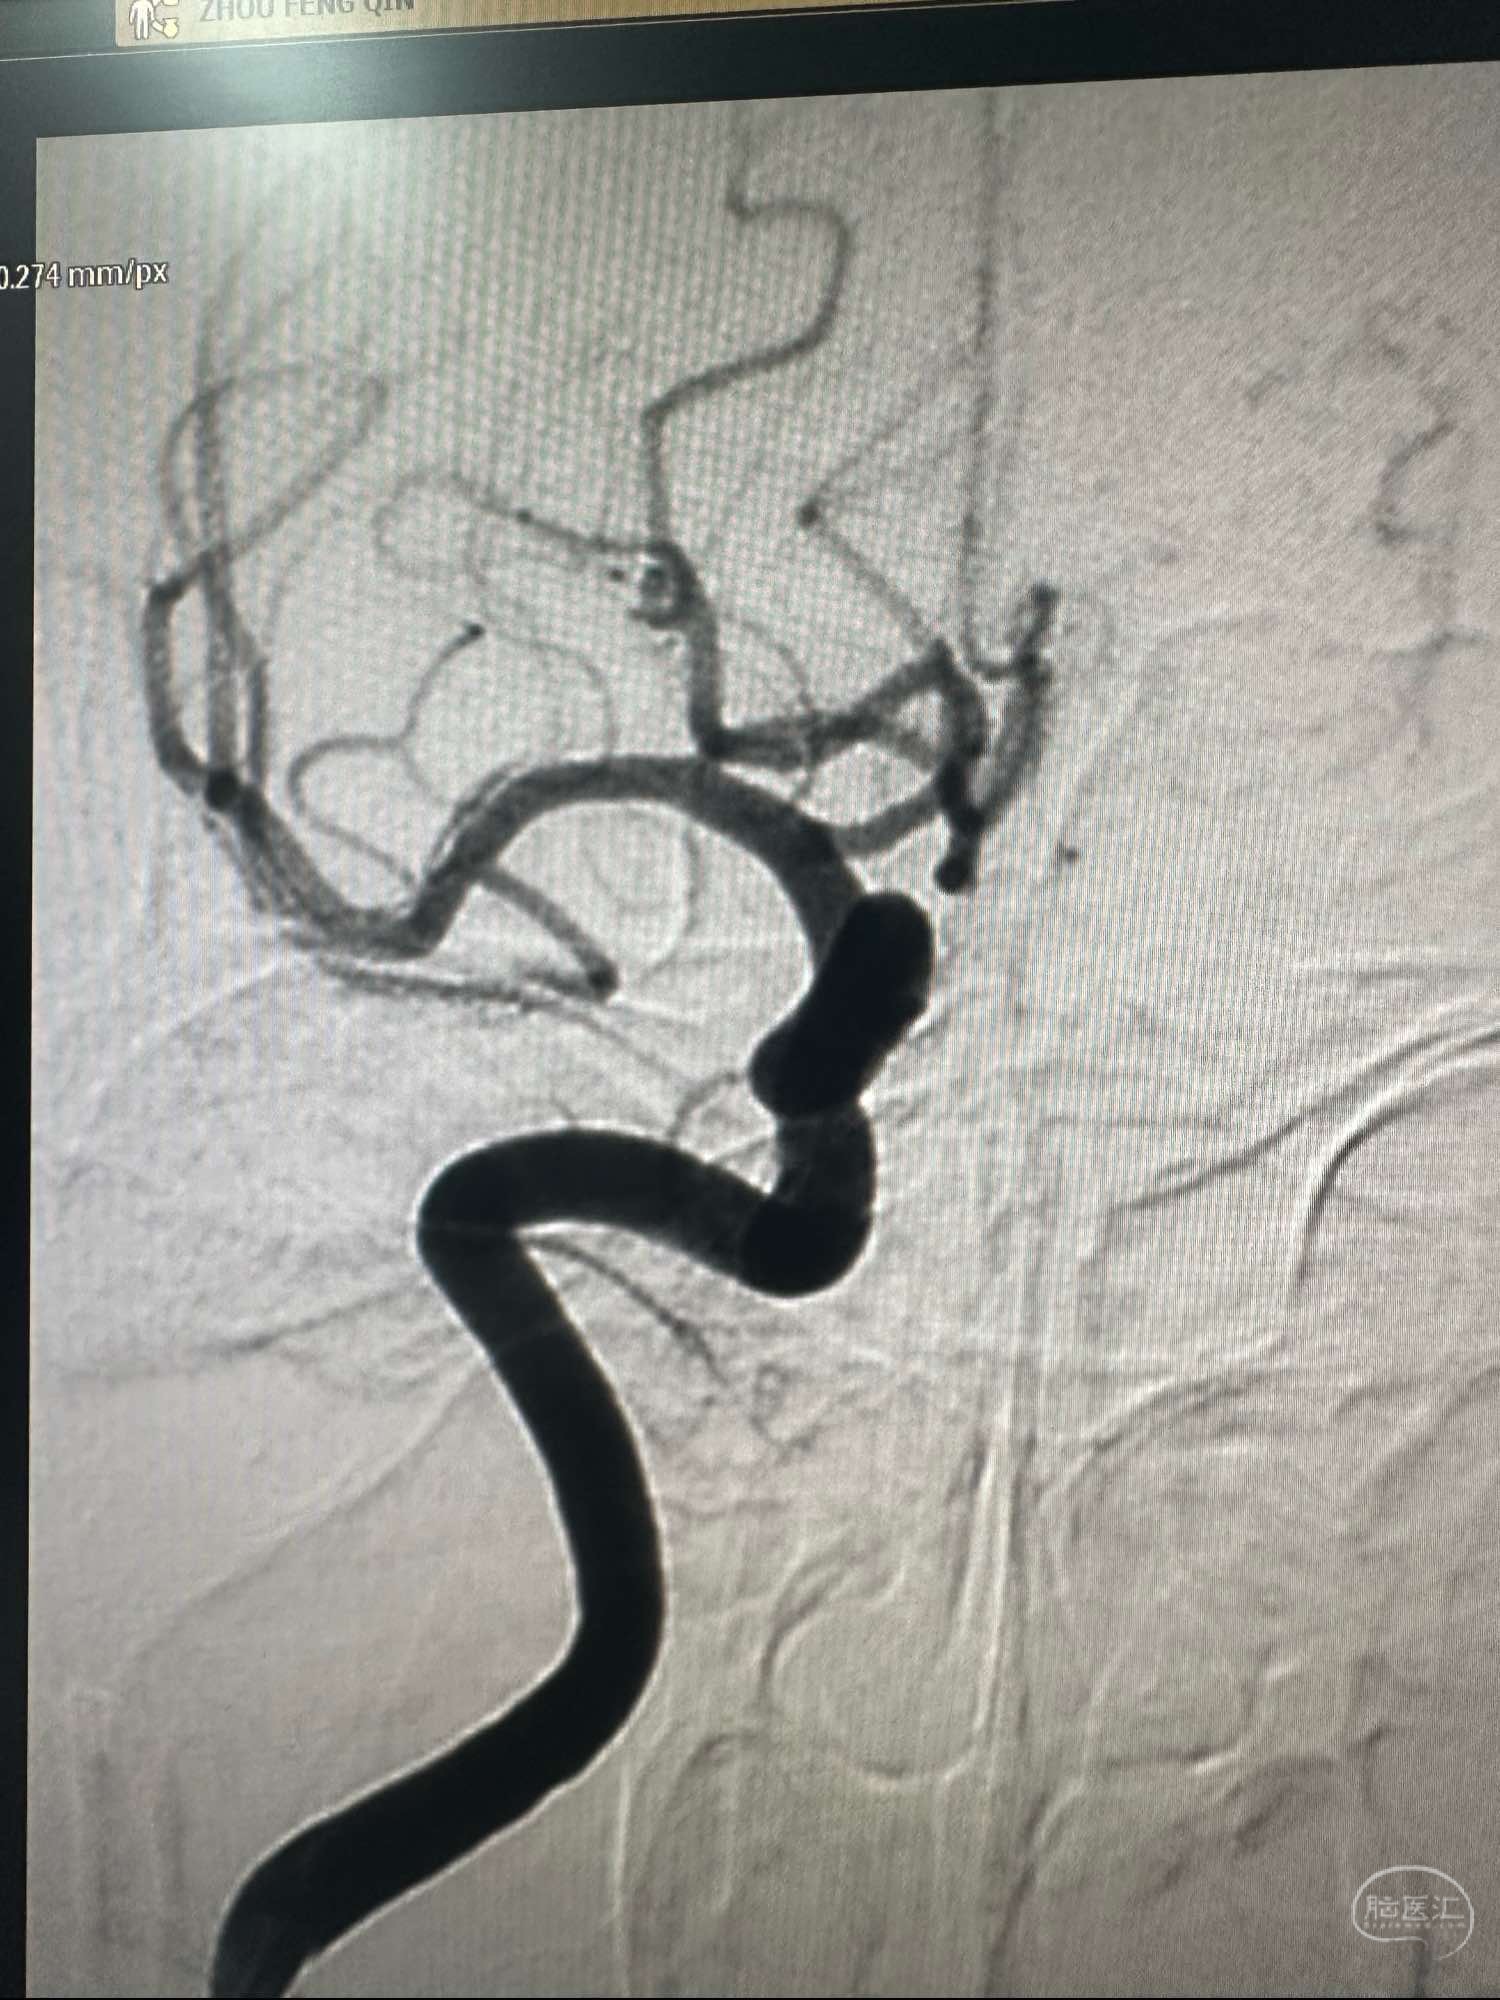

右侧颈内动脉造影正位